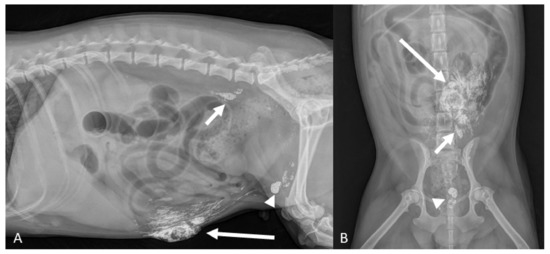

3.2. Lymph Node Drainage